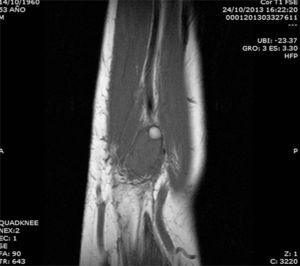

The patient was a 53-year-old man with no significant medical history. He presented with a painless mass in anterior forearm, reporting no previous injury. Physical examination confirmed the presence of a hard, immobile mass measuring less than 1cm. He came to the rheumatologic examination room, where he underwent soft tissue ultrasound (Toshiba Aplio®300). A round mass measuring less than 1cm was observed. It was iso/hypoechoic on gray scale images, was moderately well-defined, and was joined to a vessel that fed it (Fig. 1). On color Doppler, there was high echo intensity throughout the entire lesion, more intense on the periphery (Figs. 2 and 3). As there were findings that raised suspicion, such as heterogeneity, the marked vascularity and the marked Doppler signal (grade 3), magnetic resonance imaging was performed. This study revealed a round, well-defined form measuring 1cm, with hyperintensity on T1-weighted images, which pointed to a metastatic lesion (Fig. 4).